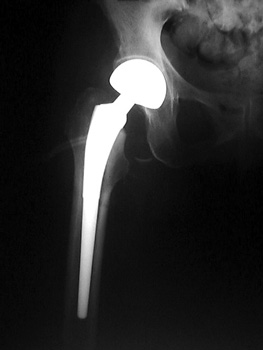

• Bipolar hemiarthroplasty

• Native acetabulum with cartilage remains

• Large metallic cup size of native femoral head contains polyethylene component with articular cavity where metallic femoral head is locked into place.

• Allows for 2 articular sites

• Large metallic cup with native acetabulum

• Metallic femoral head and polyethylene component

• Reduces stress to native acetabulum

• Metallic cup may move with respect to acetabulum

Bipolar hemiarthroplasty placed in patient with Garden IV hip fracture